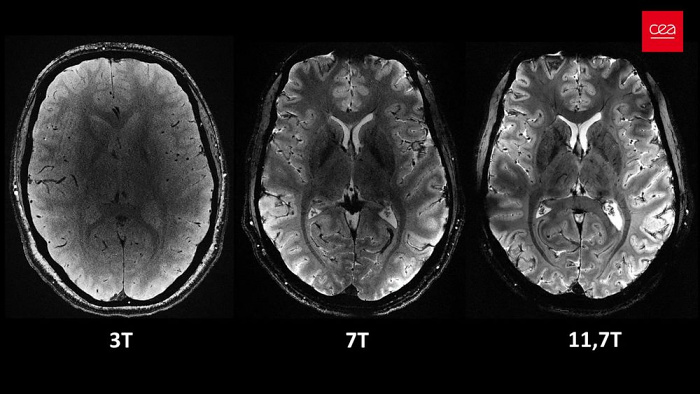

Во Франции разработан самый мощный в мире МРТ-аппарат Iseult — он способен обеспечить напряженность поля на уровне 11,7 Тесла. Это в несколько раз превосходит возможности массово применяемых МРТ-аппаратов в современных клиниках.

Главным отличием Iseult является возможность сканирования мозга в намного более высоком разрешении. Всего за 240 секунд он способен сделать снимки человеческого мозга в виде 1-миллиметровых срезов. Обычный МРТ для получения таких результатов потребует 2 часов неподвижного нахождения пациента внутри.

Несколькими годами ранее Iseult испытывался на тыквах, сейчас его протестировали на 20 добровольцах. Полученные изображения раскрывают весь потенциал технологии МРТ и позволяют лучше понять, как работает мозг. При этом, сверхмощный томограф может быть полезен не только ученым, но и медикам. С его помощью можно изучать и диагностировать такие нейродегенеративные недуги, как болезни Паркинсона и Альцгеймера.